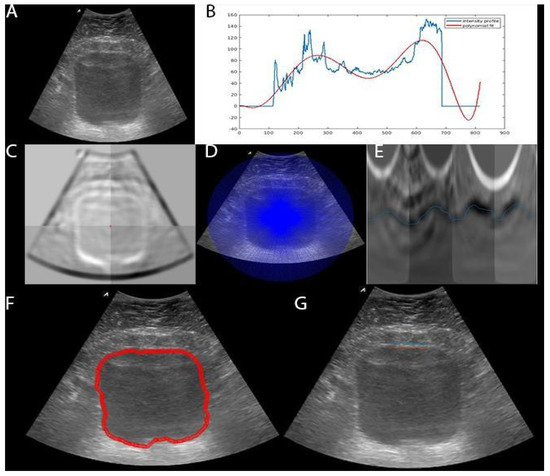

2.2. Bladder Segmentation

2.2.1. Dynamic Programming (DP)

2.2.2. Deep Learning (DL)

2.3. Bladder Wall Thickness Measurement